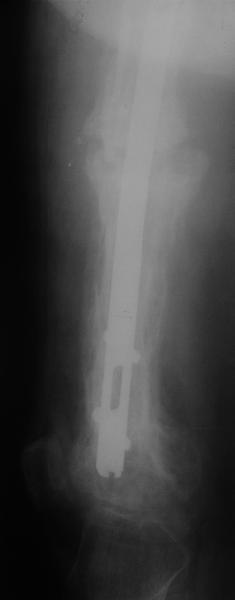

Пациент 82 лет, поступил через 5 мес. с несросшимся переломом после открытого интрамедуллярного остеосинтеза. Выполнили реостеосинтез стержнем 12 мм. ( мах. доступного нам в 2003 г.) Через 4 мес динамизация. В течении 2х лет сращения нет, тем не менее конечность опорна (ходит с тростью). От очередного реостеосинтеза отказались из-за сопутств. патологии.

PS: случай конечно не аналогичный, учитывая первичный открытый остеосинтез.